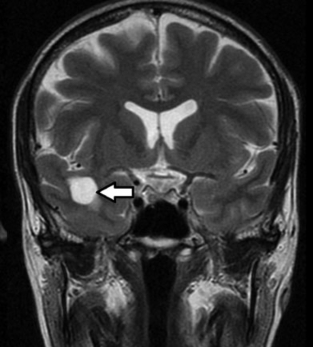

También denominados quistes glioependimales, son uniloculares con cierta dominancia frontolobar (►Fig. 4).4,8 Se originan de componentes embriológicos del tubo neural que quedan secuestrados durante el desarrollo de la sustancia blanca.4 En imágenes presentan las características de un quiste simple.4 El diagnóstico diferencial debe realizarse4,8 con:

RM de cerebro, corte coronal ponderado en T2. En el lóbulo temporal derecho se observa una imagen quística simple (flecha). Corresponde a un quiste neuroglial.